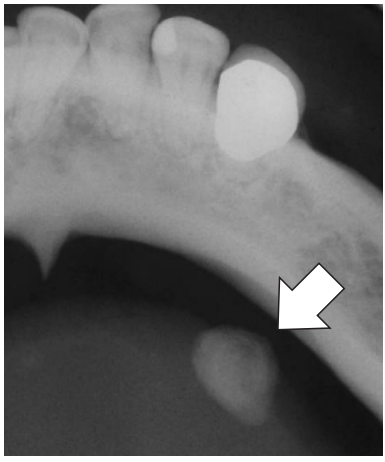

Analise a radiografia oclusal de mandibula abaixo:

Disponível em: Livro – Patologia Oral e Maxilofacial – Neville; Damn; Allen; & Bouquot. 3ª ed

De acordo com a radiografia, assinale a alternativa que descreve corretamente a hipótese diagnóstica para a imagem apontada na seta.